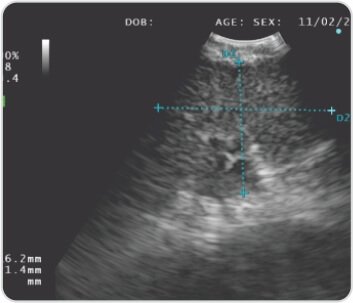

تُظهر الأشعة السينية للصدر اتساعًا فائقًا للمنصف. يُظهر التصوير المقطعي للصدر تضخم العقد اللمفية المنصفية مع عقدة مجاورة للرغامى العلوية اليمنى بقياس 2*3 سم، وتظهر حمة الرئة عقيدات انشطارية. تم إجراء EBUS TBNA تحت التخدير العام وكان اختبار ROSE (الفحص السريع في الموقع) إيجابيًا بالنسبة للالتهاب الحبيبي غير المسبب للحالة. تم إجراء تنظير القصبات في وقت واحد والذي أظهر وجود غشاء مخاطي عقيدي يوحي بوجود الساركويد.

الشكل 5: حجم العقدة الليمفاوية العقدة المجاورة للرغامى (4R)